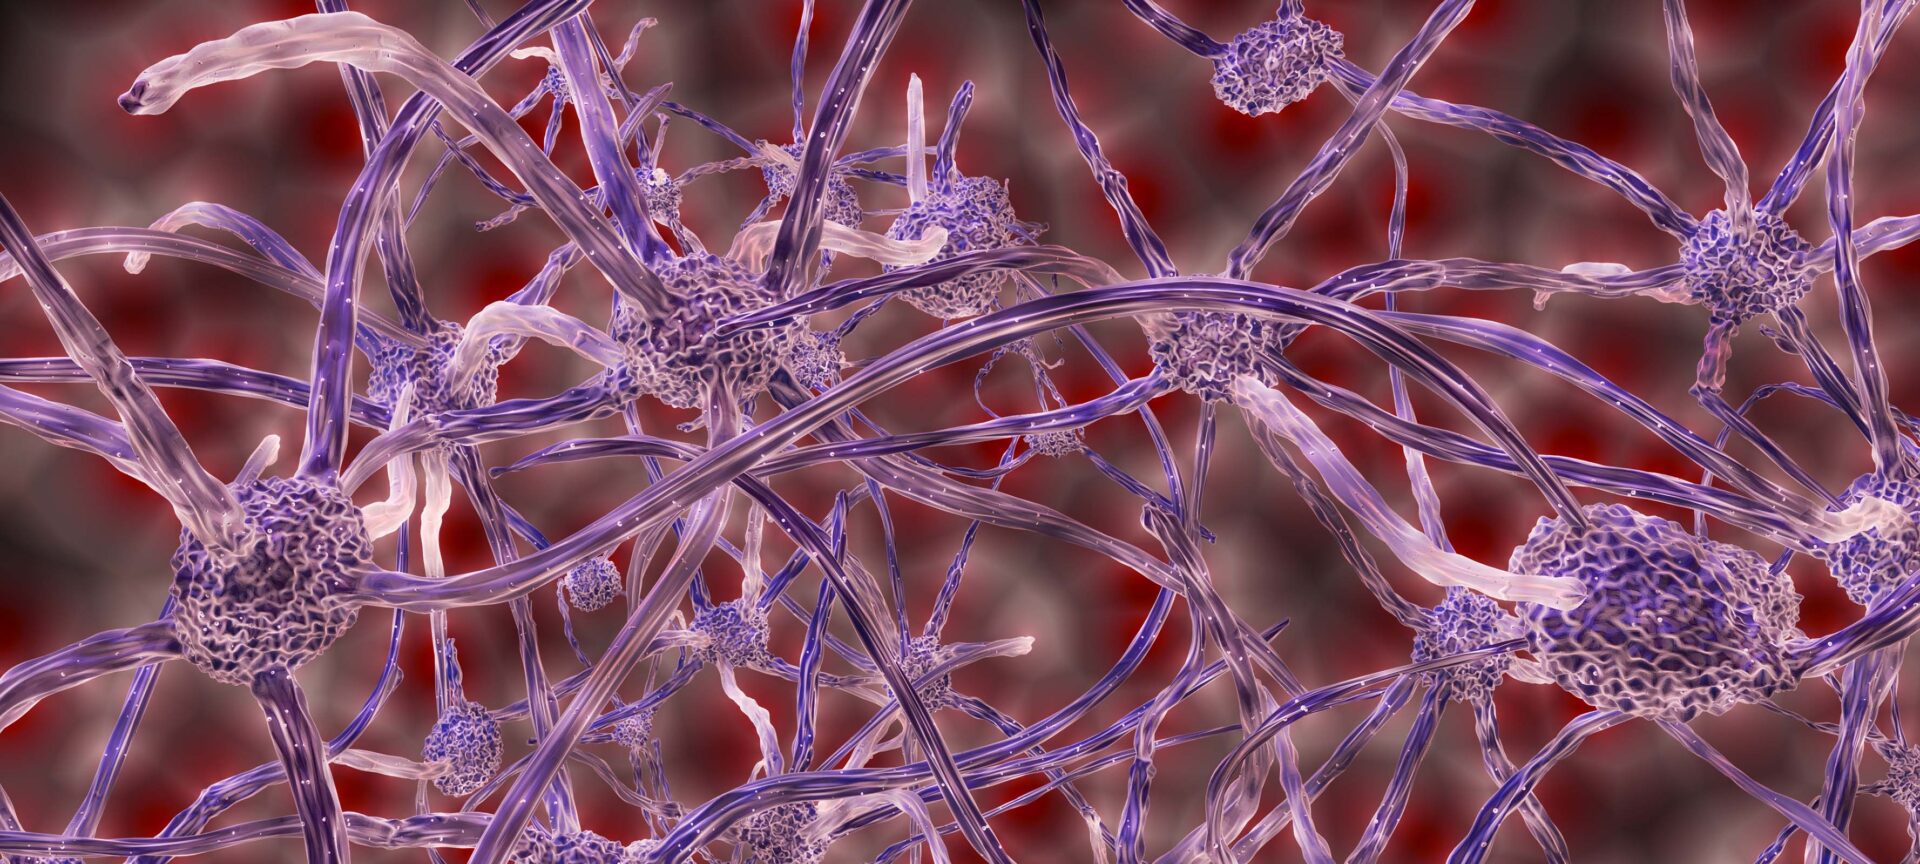

Human stem cells coaxed to mimic the very early central nervous system

The first organized stem cell culture model that resembles all three sections of the embryonic brain and spinal cord could shed light on developmental brain diseases.

Novel collaboration to probe brain activity in unprecedented detail

A pilot program will bring together researchers from different universities to collaborate on advancing research that may lead to a better understanding of the human brain.

Improved neural probe can pose precise questions without losing parts of the answers

It will now be possible to study brain activity when timing is important, such as the consolidation of memory.

Research on neural probe that sheds multicolor light on the complexities of the brain recognized for its impact

Prof. Euisik Yoon and his team are recognized for their work designing low-noise, multisite/multicolor optoelectrodes that will help neurologists learn more about neural connectivity in the brain.

Next generation neural probe leads to expanded understanding of the brain

The hectoSTAR probe, with 128 stimulating micro-LEDs and 256 recording electrodes integrated in the same neural probe, was designed for some stellar brain mapping projects